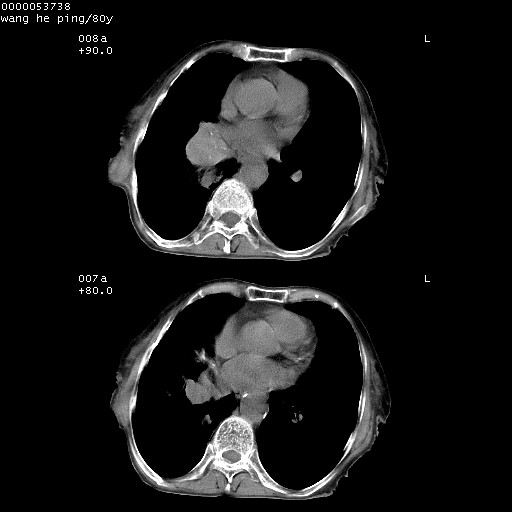

以下是引用黑白光影在2008-8-28 22:33:00的发言:[br]右肺中央型肺癌伴阻塞性肺炎,肺癌肺转移。

以下是引用lshx在2008-8-28 22:06:00的发言:[br]1.右肺中心型肺癌伴阻塞性肺炎,不除外双 肺早期转移。[br]2.心包积液。

以下是引用随光逐影在2008-8-29 7:40:00的发言:[br]1)右肺中心型肺癌伴阻塞性肺炎,肺内转移。2)心包积液(少量)。

以下是引用wqs571018在2008-8-28 21:56:00的发言:[br]右肺中心型肺癌伴阻塞性肺炎可能。

以下是引用liuyue在2008-8-28 22:46:00的发言:[br]1.右肺中心型肺癌伴阻塞性肺炎。[br]2.心包积液(少量)。